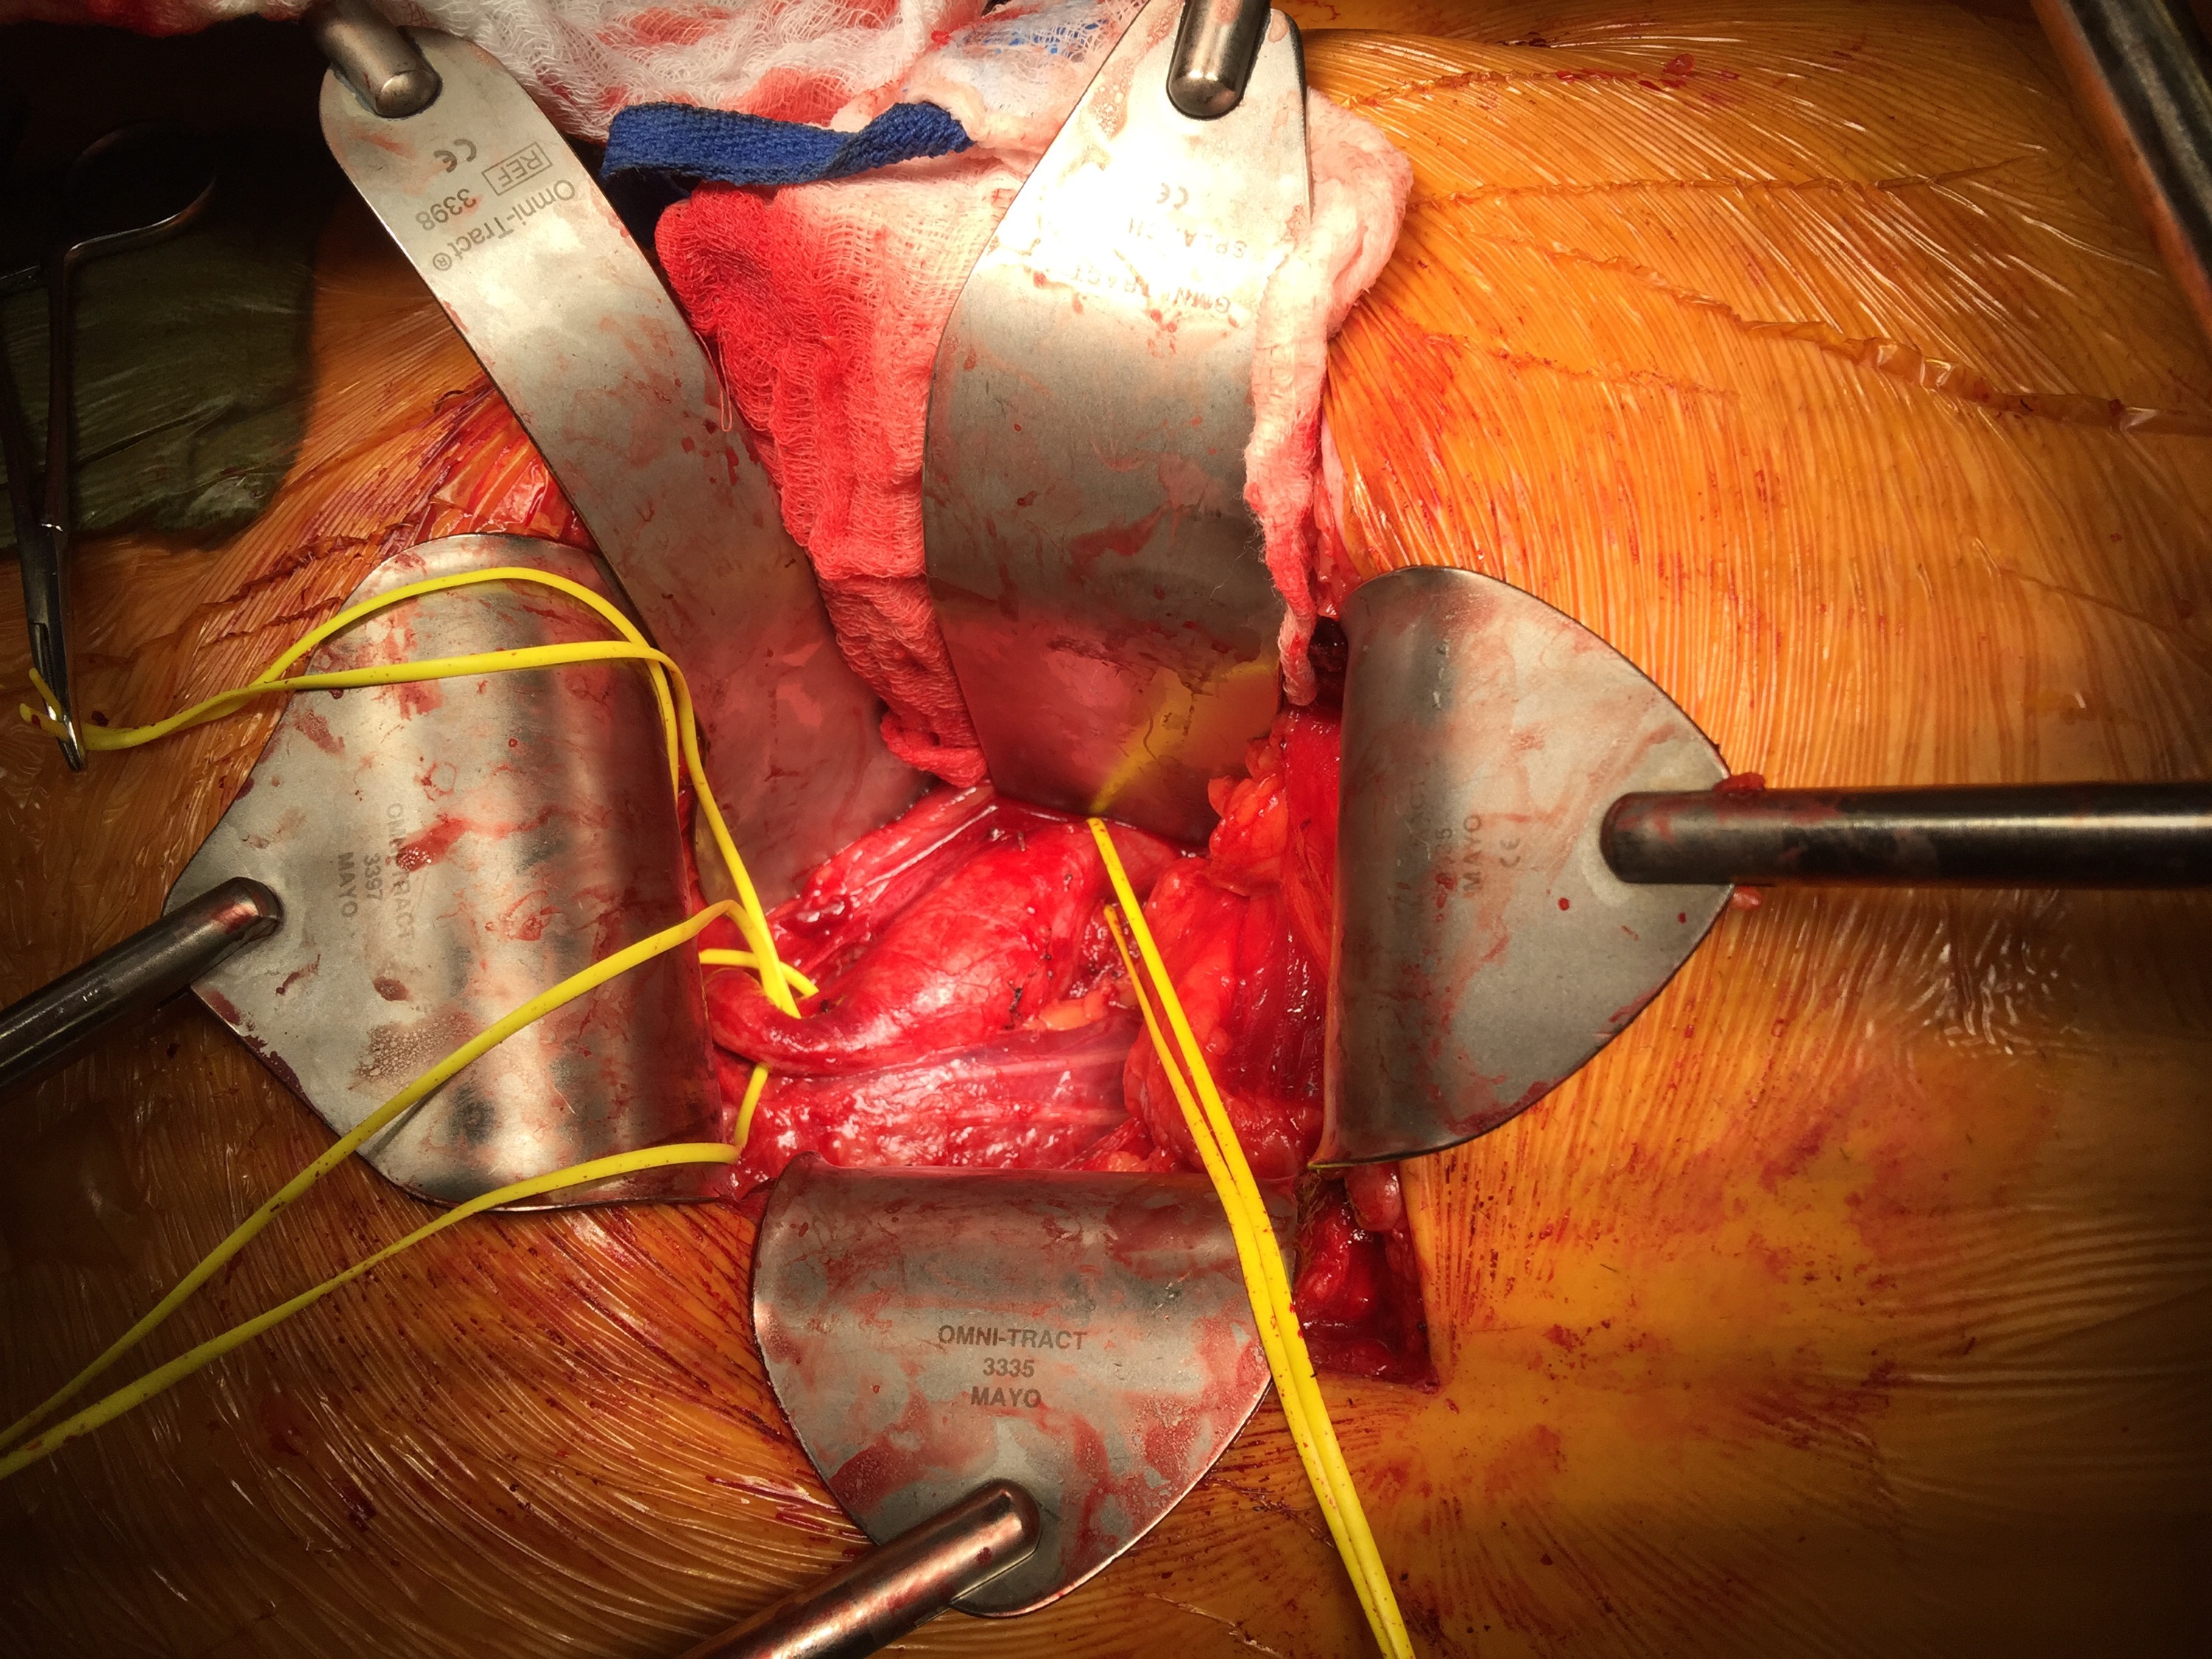

The final option of a femoral or external iliac to internal iliac bypass after extension across the bifurcation to the external iliac artery is still a reasonable choice, although it seems to be receding into history.